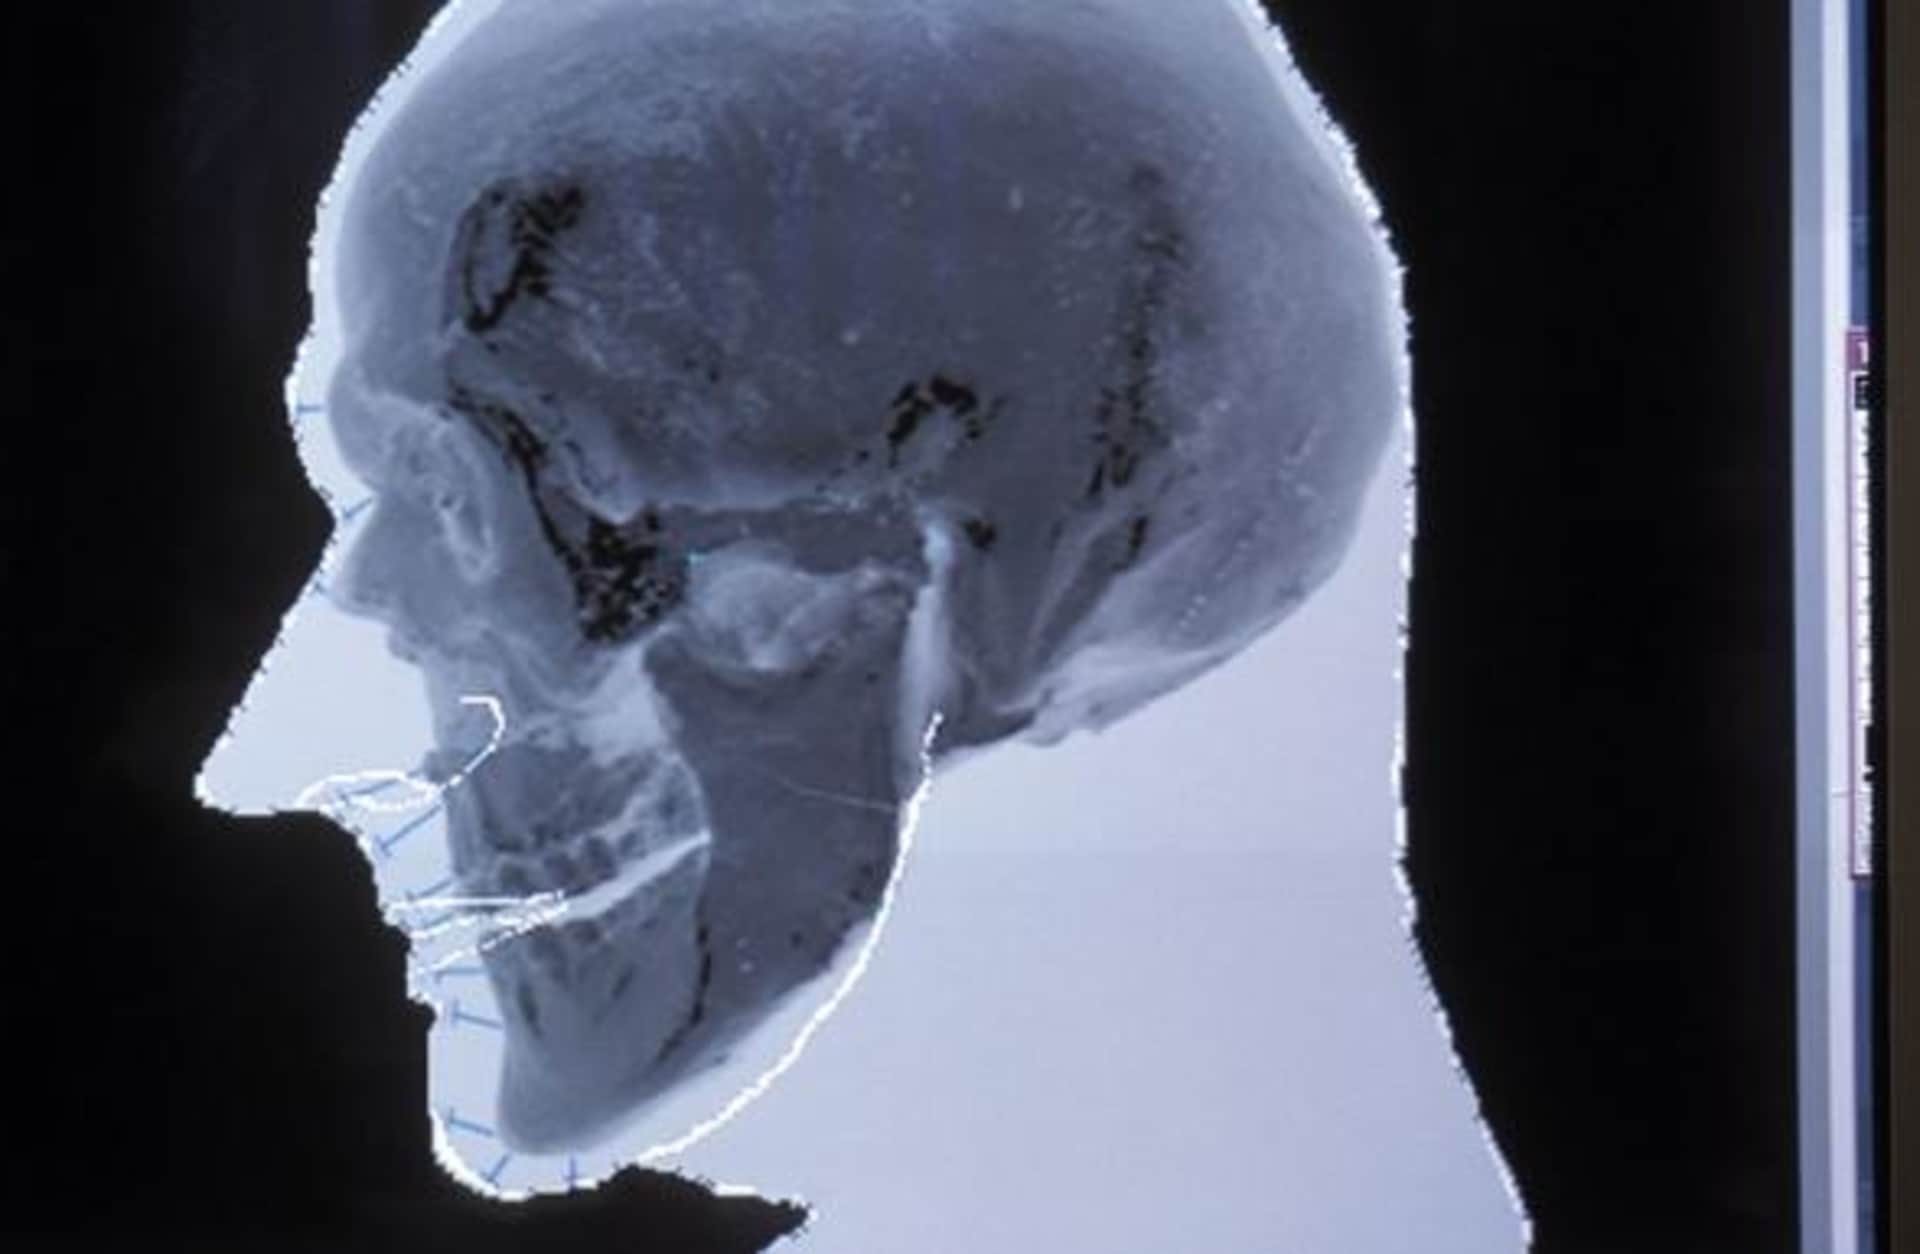

The probable shape of Otzi's face is produced and superimposed over the digital image of his actual skull as part of the facial reconstruction. (Photo by Patrick Landmann/Getty Images)

The probable shape of Otzi’s face is produced and superimposed over the digital image of his actual skull as part of the facial reconstruction. (Photo by Patrick Landmann/Getty Images)